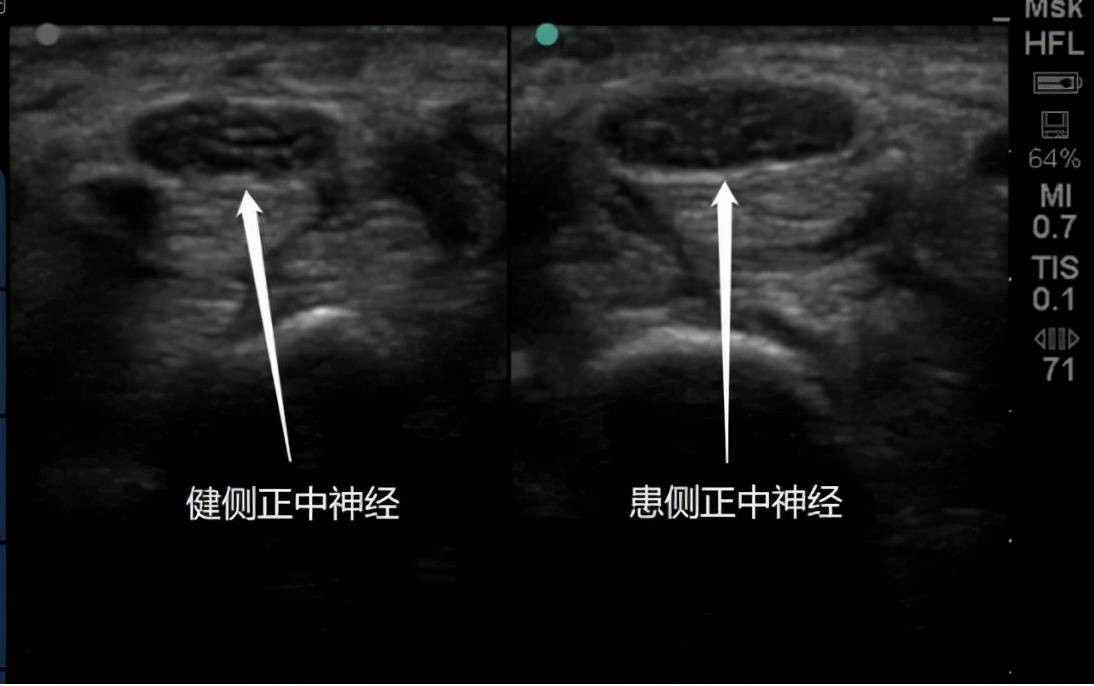

▲超声影像显示双侧正中神经对比